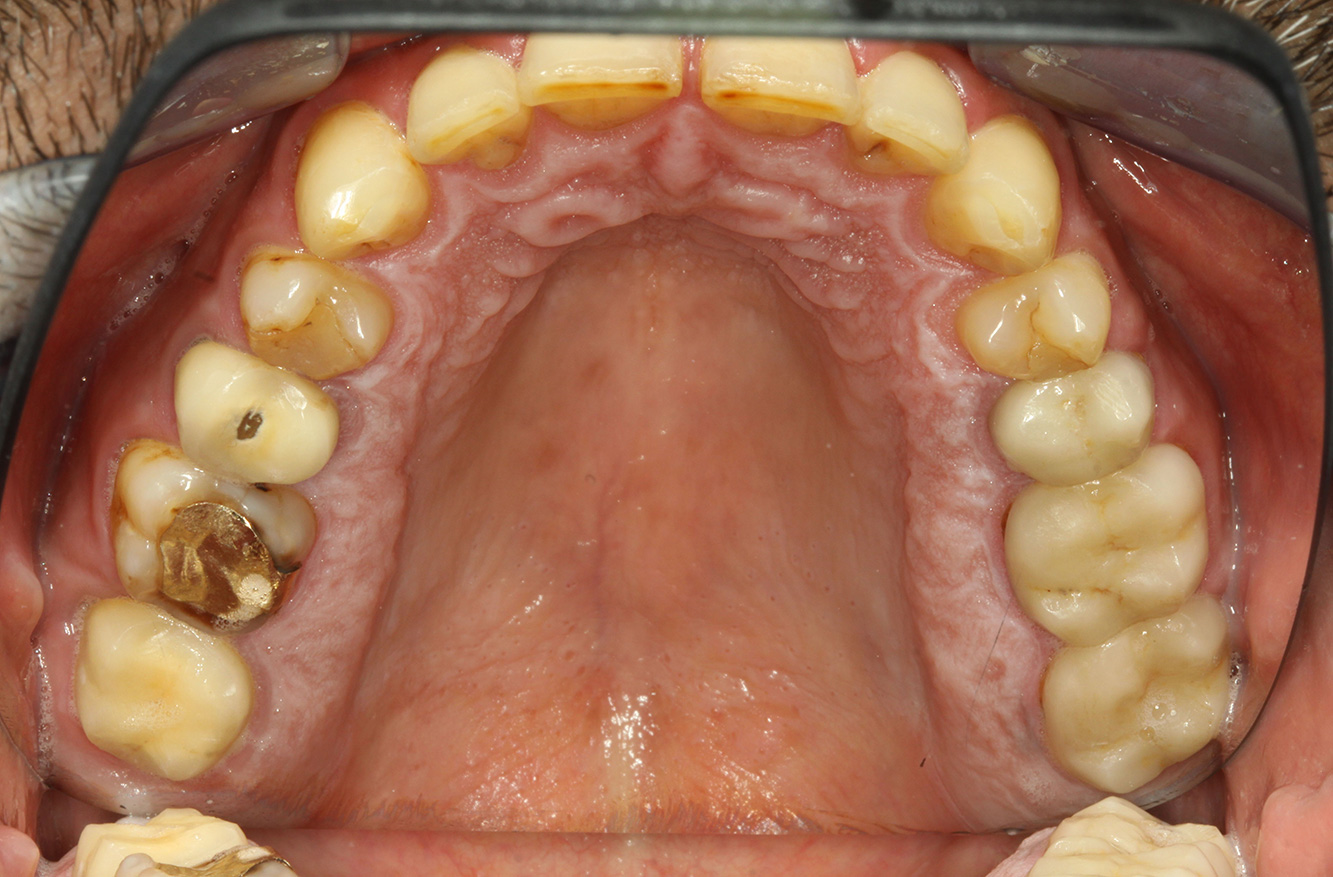

Der Patient ist 39 Jahre mit Z.n. Herzklappenersatz wegen Klappenfehlers und Endokarditis. Als Antikoagulans (Gerinnungshemmer) wird regelmäßig ASS 100 eingenommen. Aus dem Bereich Lebensstil ist die Ernährungsweise als kariesfördernd einzustufen, da mit hoher Regelmäßigkeit zuckerhaltige Lebensmittel sowie sechs bis sieben Mahlzeiten täglich verzehrt werden. Die Mundgesundheit des Patienten zeigt ein mittleres Kariesrisiko mit aktiven Läsionen. Das Parodontitisrisiko ist niedrig, es besteht eine Gingivitis. Es ergeben sich folgende Empfehlungen für die Prophylaxebehandlung.

Für die Prophylaxesitzung lassen sich keine spezifischen Instrumentierungsempfehlungen ableiten. Durch den gezielten Einsatz von Pulverstrahl und rotierend Polieren können Plaque und Verfärbungen an den Restaurationsrändern schonend entfernt und Wiederbesiedlungsnischen für kariogene Bakterien reduziert werden (19).

Zur weiteren Unterstützung der Kariesprävention ist eine Fluoridierung, besonders um der Neuentstehung im Bereich der Restaurationsränder vorzubeugen, und eine Versiegelung der Wurzeloberflächen empfehlenswert. Beide Maßnahmen können die angegebene Temperatursensibilität der Zähne reduzieren.